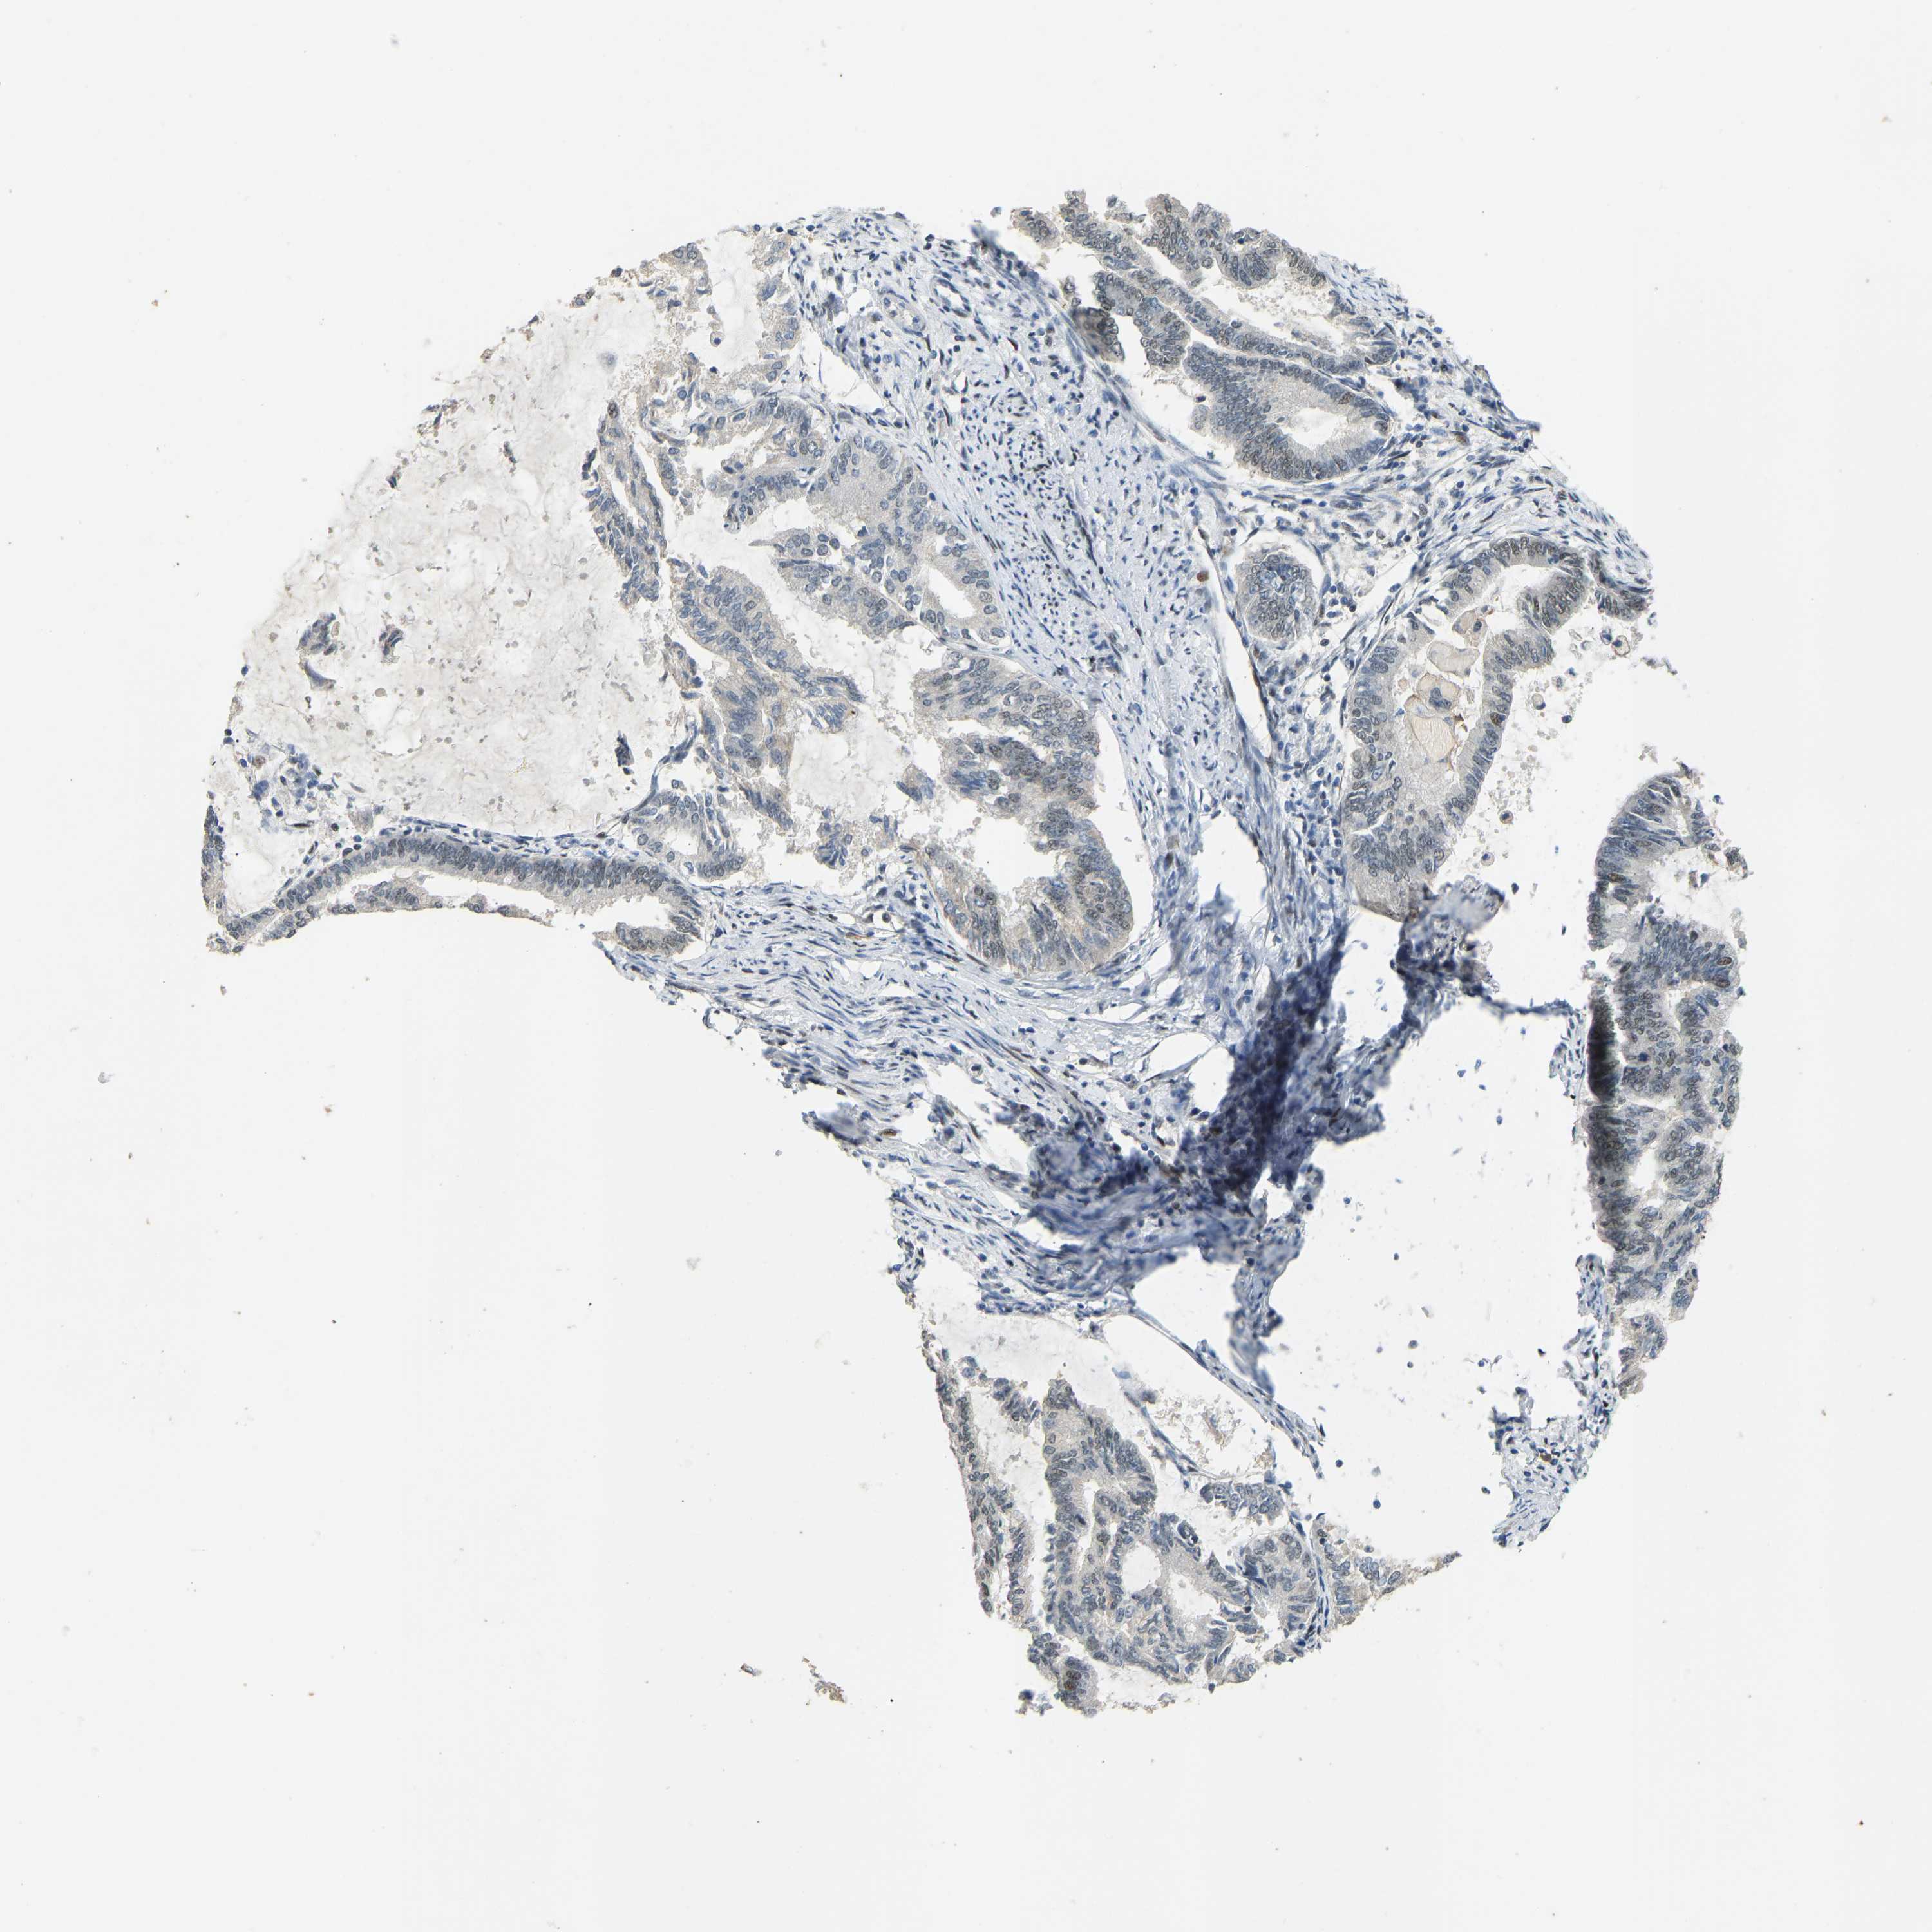

ENDOMETRIAL CANCER - Protein expressioni

A mouse-over function shows sample information and annotation data. Click on an image to view it in a full screen mode. Samples can be filtered based on level of antibody staining by selecting one or several of the following categories: high, medium, low and not detected. The assay and annotation is described here.

Note that samples used for immunohistochemistry by the Human Protein Atlas do not correspond to samples in the TCGA dataset.

Antibody stainingi

Antibody staining in the annotated cell types in the current human tissue is reported as not detected, low, medium, or high, based on conventional immunohistochemistry profiling in selected tissues. This score is based on the combination of the staining intensity and fraction of stained cells.

Each image is clickable and will lead to virtual microscopy that enables deeper exploration of all samples and also displays staining intensity scores, fraction scores and subcellular localization as well as patient and tissue information for each sample.

Antibody HPA017998

Antibody HPA018864

Staining

High

Medium

Low

Not detected

Intensity

Strong

Moderate

Weak

Negative

Quantity

>75%

75%-25%

<25%

None

Location

Nuclear

Cytoplasmic/membranous

Cytoplasmic/membranous,nuclear

Adenocarcinoma, NOS